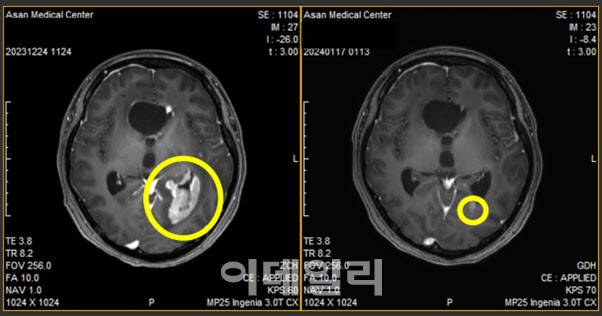

에이비온은 1일(현지시간) 교모세포종 환자에게 바바메킵을 투여한 결과, 투약 7일 만에 뇌압 상승이 멈췄다고 밝혔다. 특히 해당 환자는 바바메킵 투약 16일째 종양 크기가 90%가량 줄어들었다. 이 기간 약물 부작용은 없었다. 교모세포종은 뇌에서 발생하는 악성 뇌종양이다. 이 종양은 빠르게 성장하고 뇌 조직을 침범하는 특징이 있다.

윤 교수는 “올 1월부터 교모세포종 환자에게 바바메킵을 매일 800㎎씩 투여했다”며 “이번 결과를 통해 바바메킵이 비소세포폐암을 넘어 교모세포종으로까지 확장 가능성을 보였다”고 평가했다. 이어 “이를 토대로 바바메킵 적응증 확장을 위해 회사와 추가 임상을 논의 중”이라고 덧붙였다.